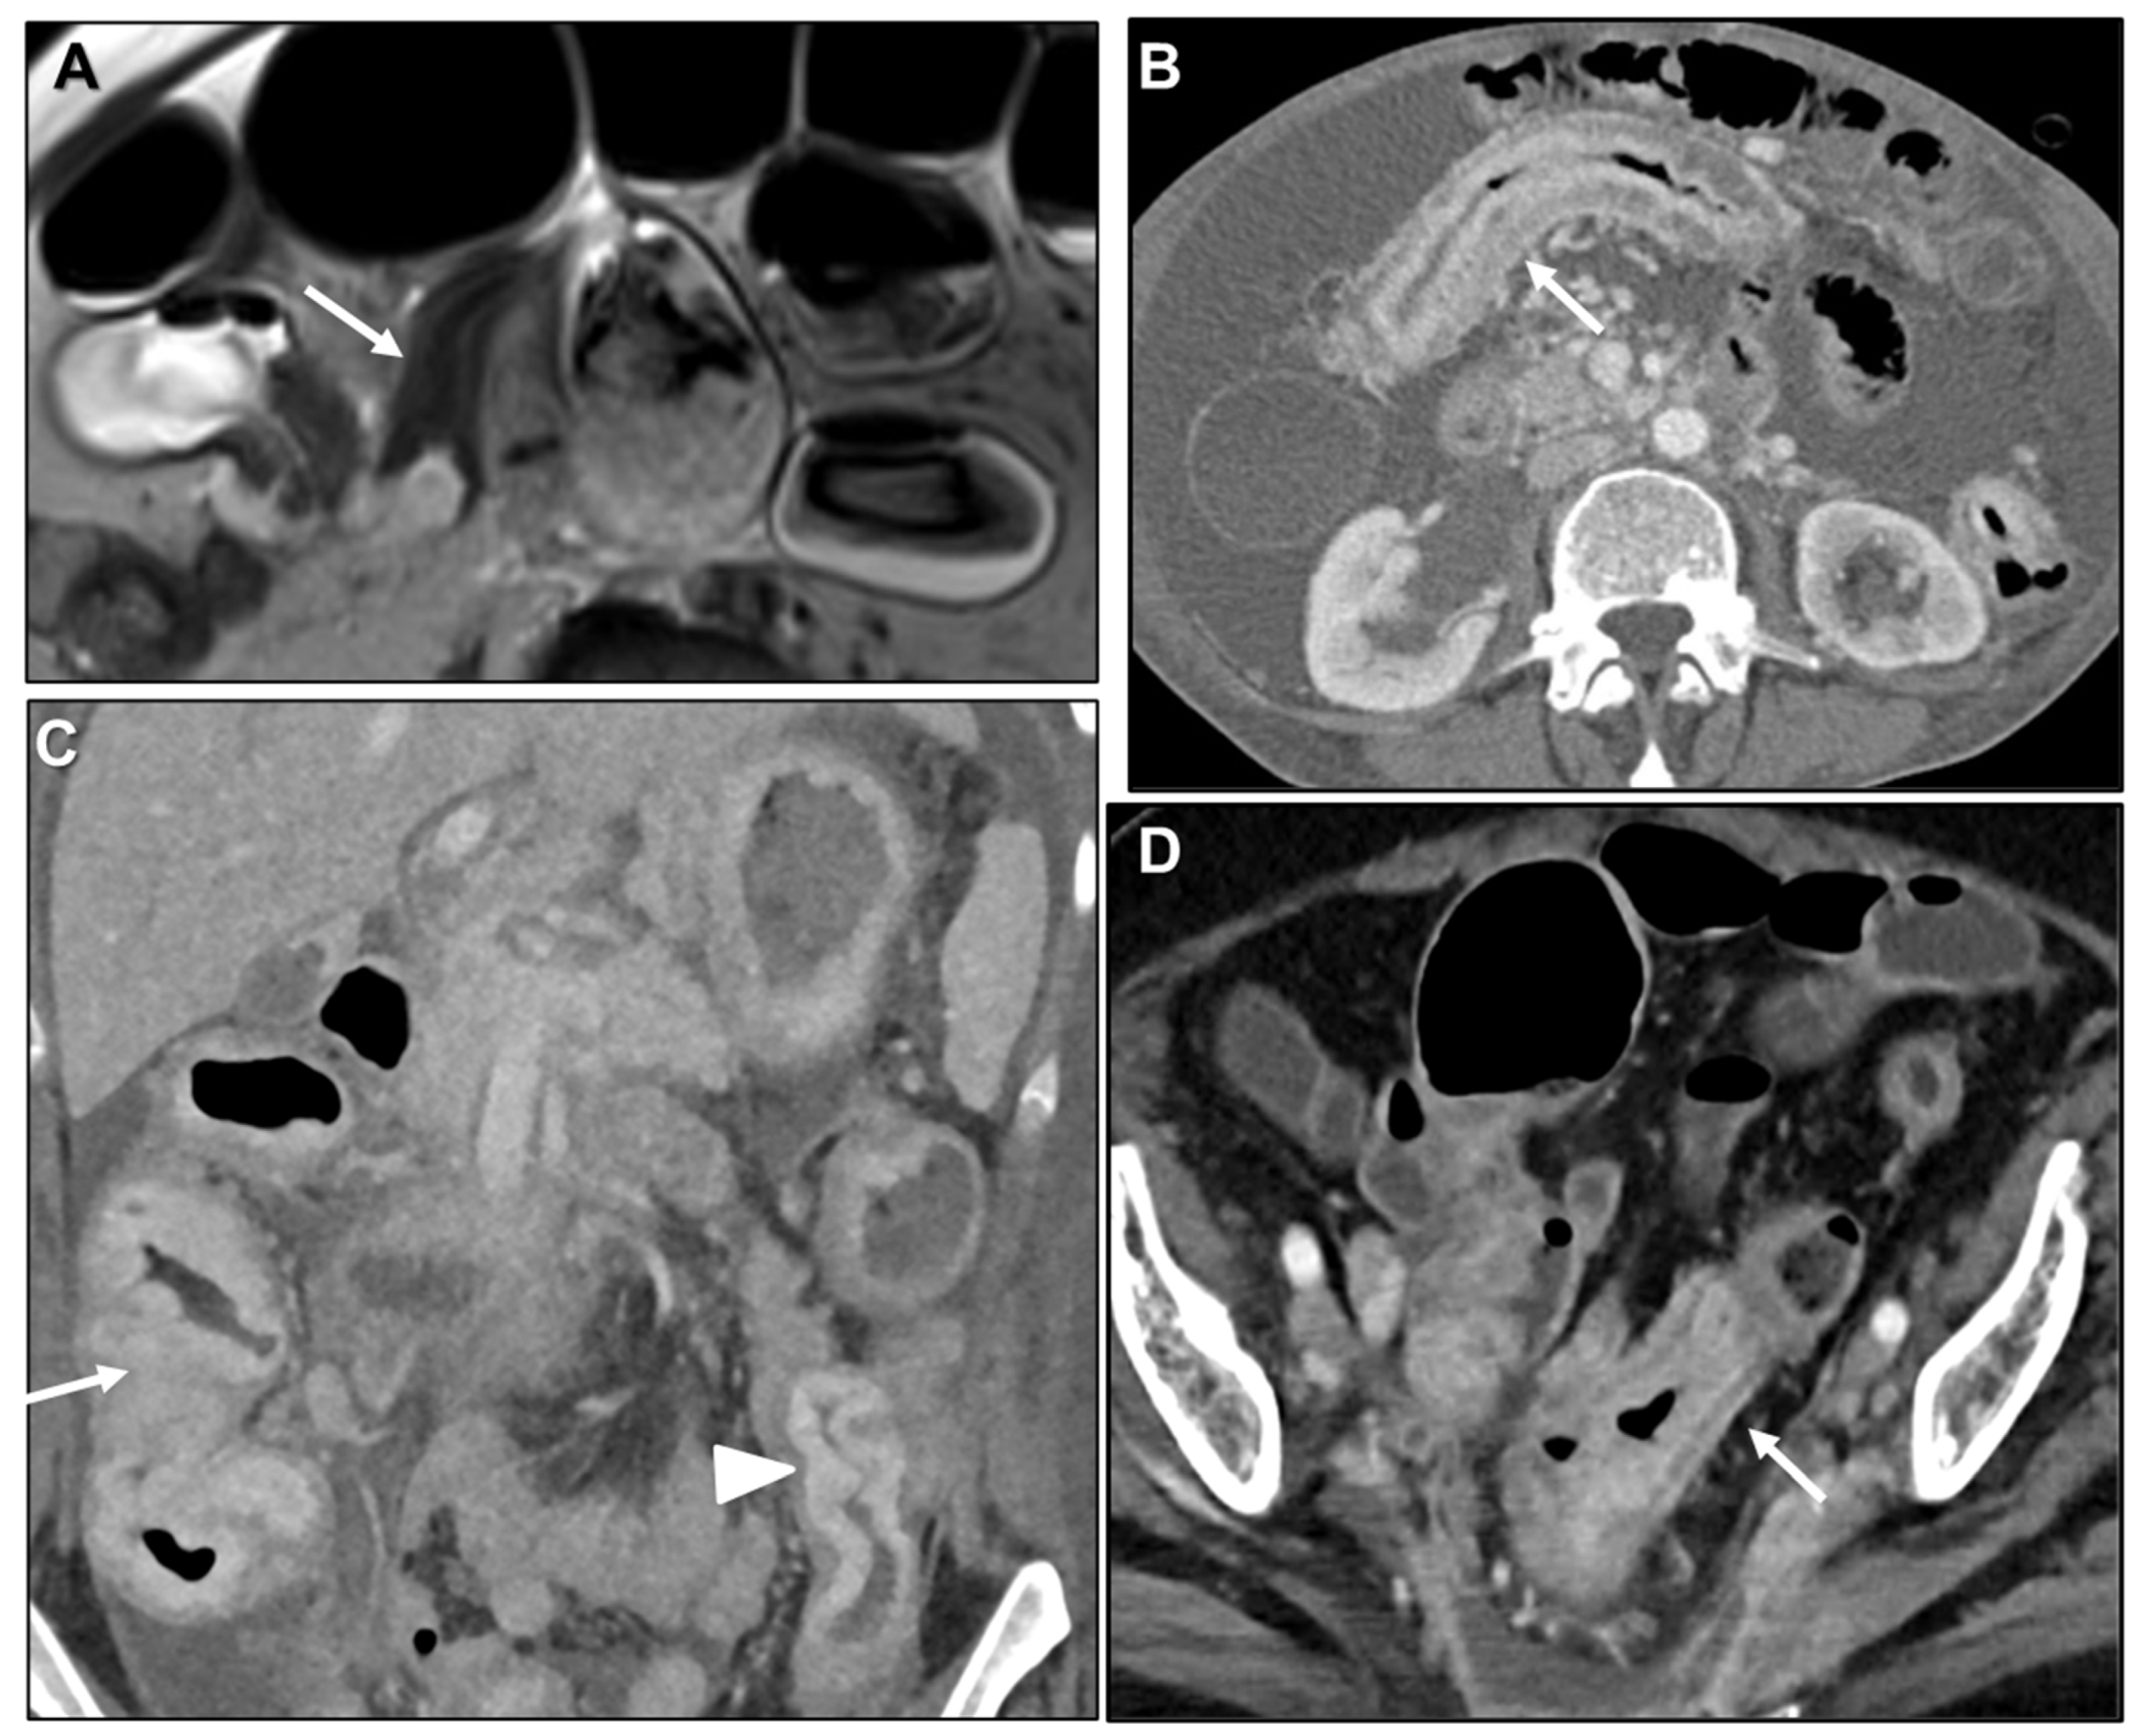

Malignant Target Sign

Homogeneous Delayed Enhancement

Concentric Ring Pattern

Length

- Gollub, M.J.; Schwartz, M.B.; Shia, J. Scirrhous metastases to the gastrointestinal tract at CT: The malignant target sign. AJR Am. J. Roentgenol. 2009, 192, 936–940. [Google Scholar] [CrossRef][Green Version]

- Balthazar, E.J.; Siegel, S.E.; Megibow, A.J.; Scholes, J.; Gordon, R. CT in patients with scirrhous carcinoma of the GI tract: Imaging findings and value for tumor detection and staging. AJR Am. J. Roentgenol. 1995, 165, 839–845. [Google Scholar] [CrossRef]

- Burgain, C.; Germain, A.; Bastien, C.; Orry, X.; Choné, L.; Claudon, M.; Laurent, V. Computed tomography features of gastrointestinal linitis plastica: Spectrum of findings in early and delayed phase imaging. Abdom. Radiol. 2016, 41, 1370–1377. [Google Scholar] [CrossRef]